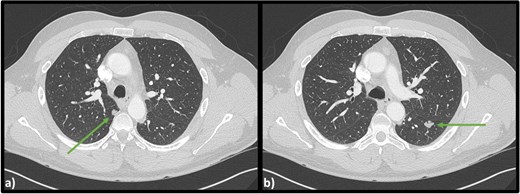

Computed tomography (CT) scans revealed no injuries, however bilateral lobulated lower lobe pulmonary masses were identified measuring 15 × 11 × 14 mm on the left and 9 × 10 × 10 mm on the right (Fig. 1).

Axial CT scan of the chest indicating (a) lobulated lesion in apical segment of right lower lobe (9 × 10 × 10 mm) and (b) secondary lobulated lesion present in left lower lobe (15 × 11 × 14 mm).